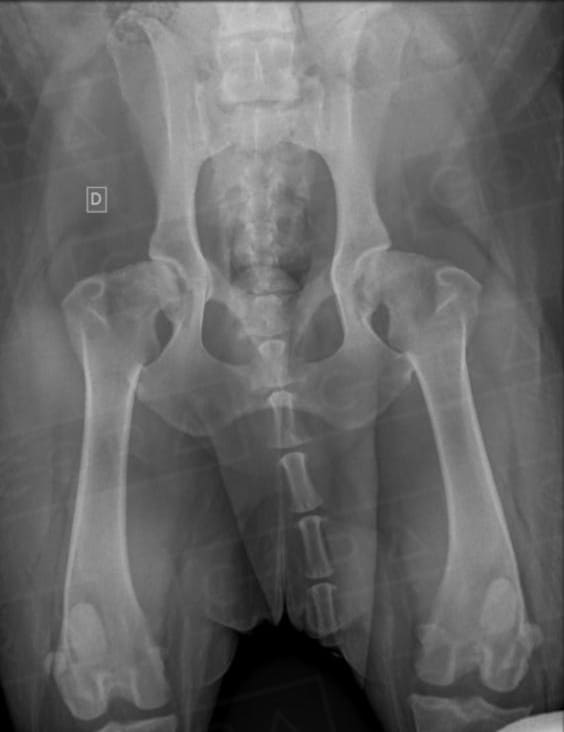

DISPLASIA COXOFEMORAL

A sinais clínicos (DCF) é uma doença de característica genética e poligênica envolvendo uma ou ambas as articulações do quadril, causada pela instabilidade do quadril, levando a incongruência articular e desenvolvimento de osteoartose.

O diagnóstico é baseado na anamnese, exame físico e radiográfico simples. O diagnóstico precoce, em filhotes ainda assintomáticos, pode ser feito por meio do PennHIP, técnica de raio-x por distração articular, que estima o grau de instabilidade do quadril e risco de desenvolvimento de osteoartrose. O diagnóstico precoce possibilita um melhor prognóstico e mais qualidade de vida ao animal.